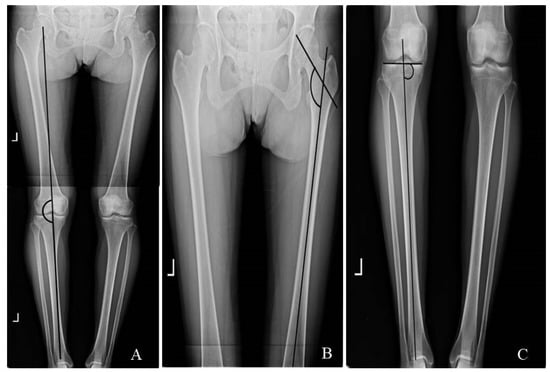

2.2. Radiographic Evaluation